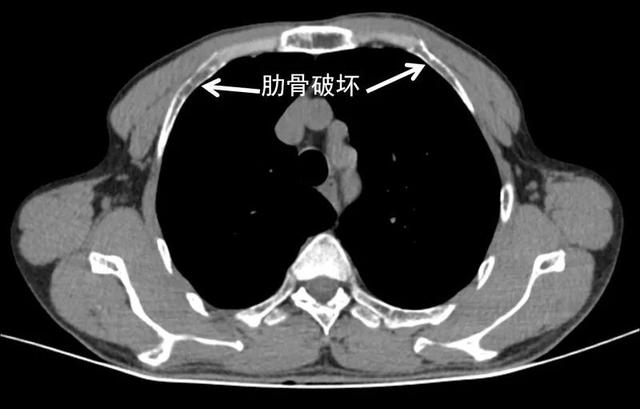

肋骨骨质破坏

胸部ct见多处肋骨破坏

胸廓骨质破坏

这个骨质破坏在哪里?右侧第六肋骨